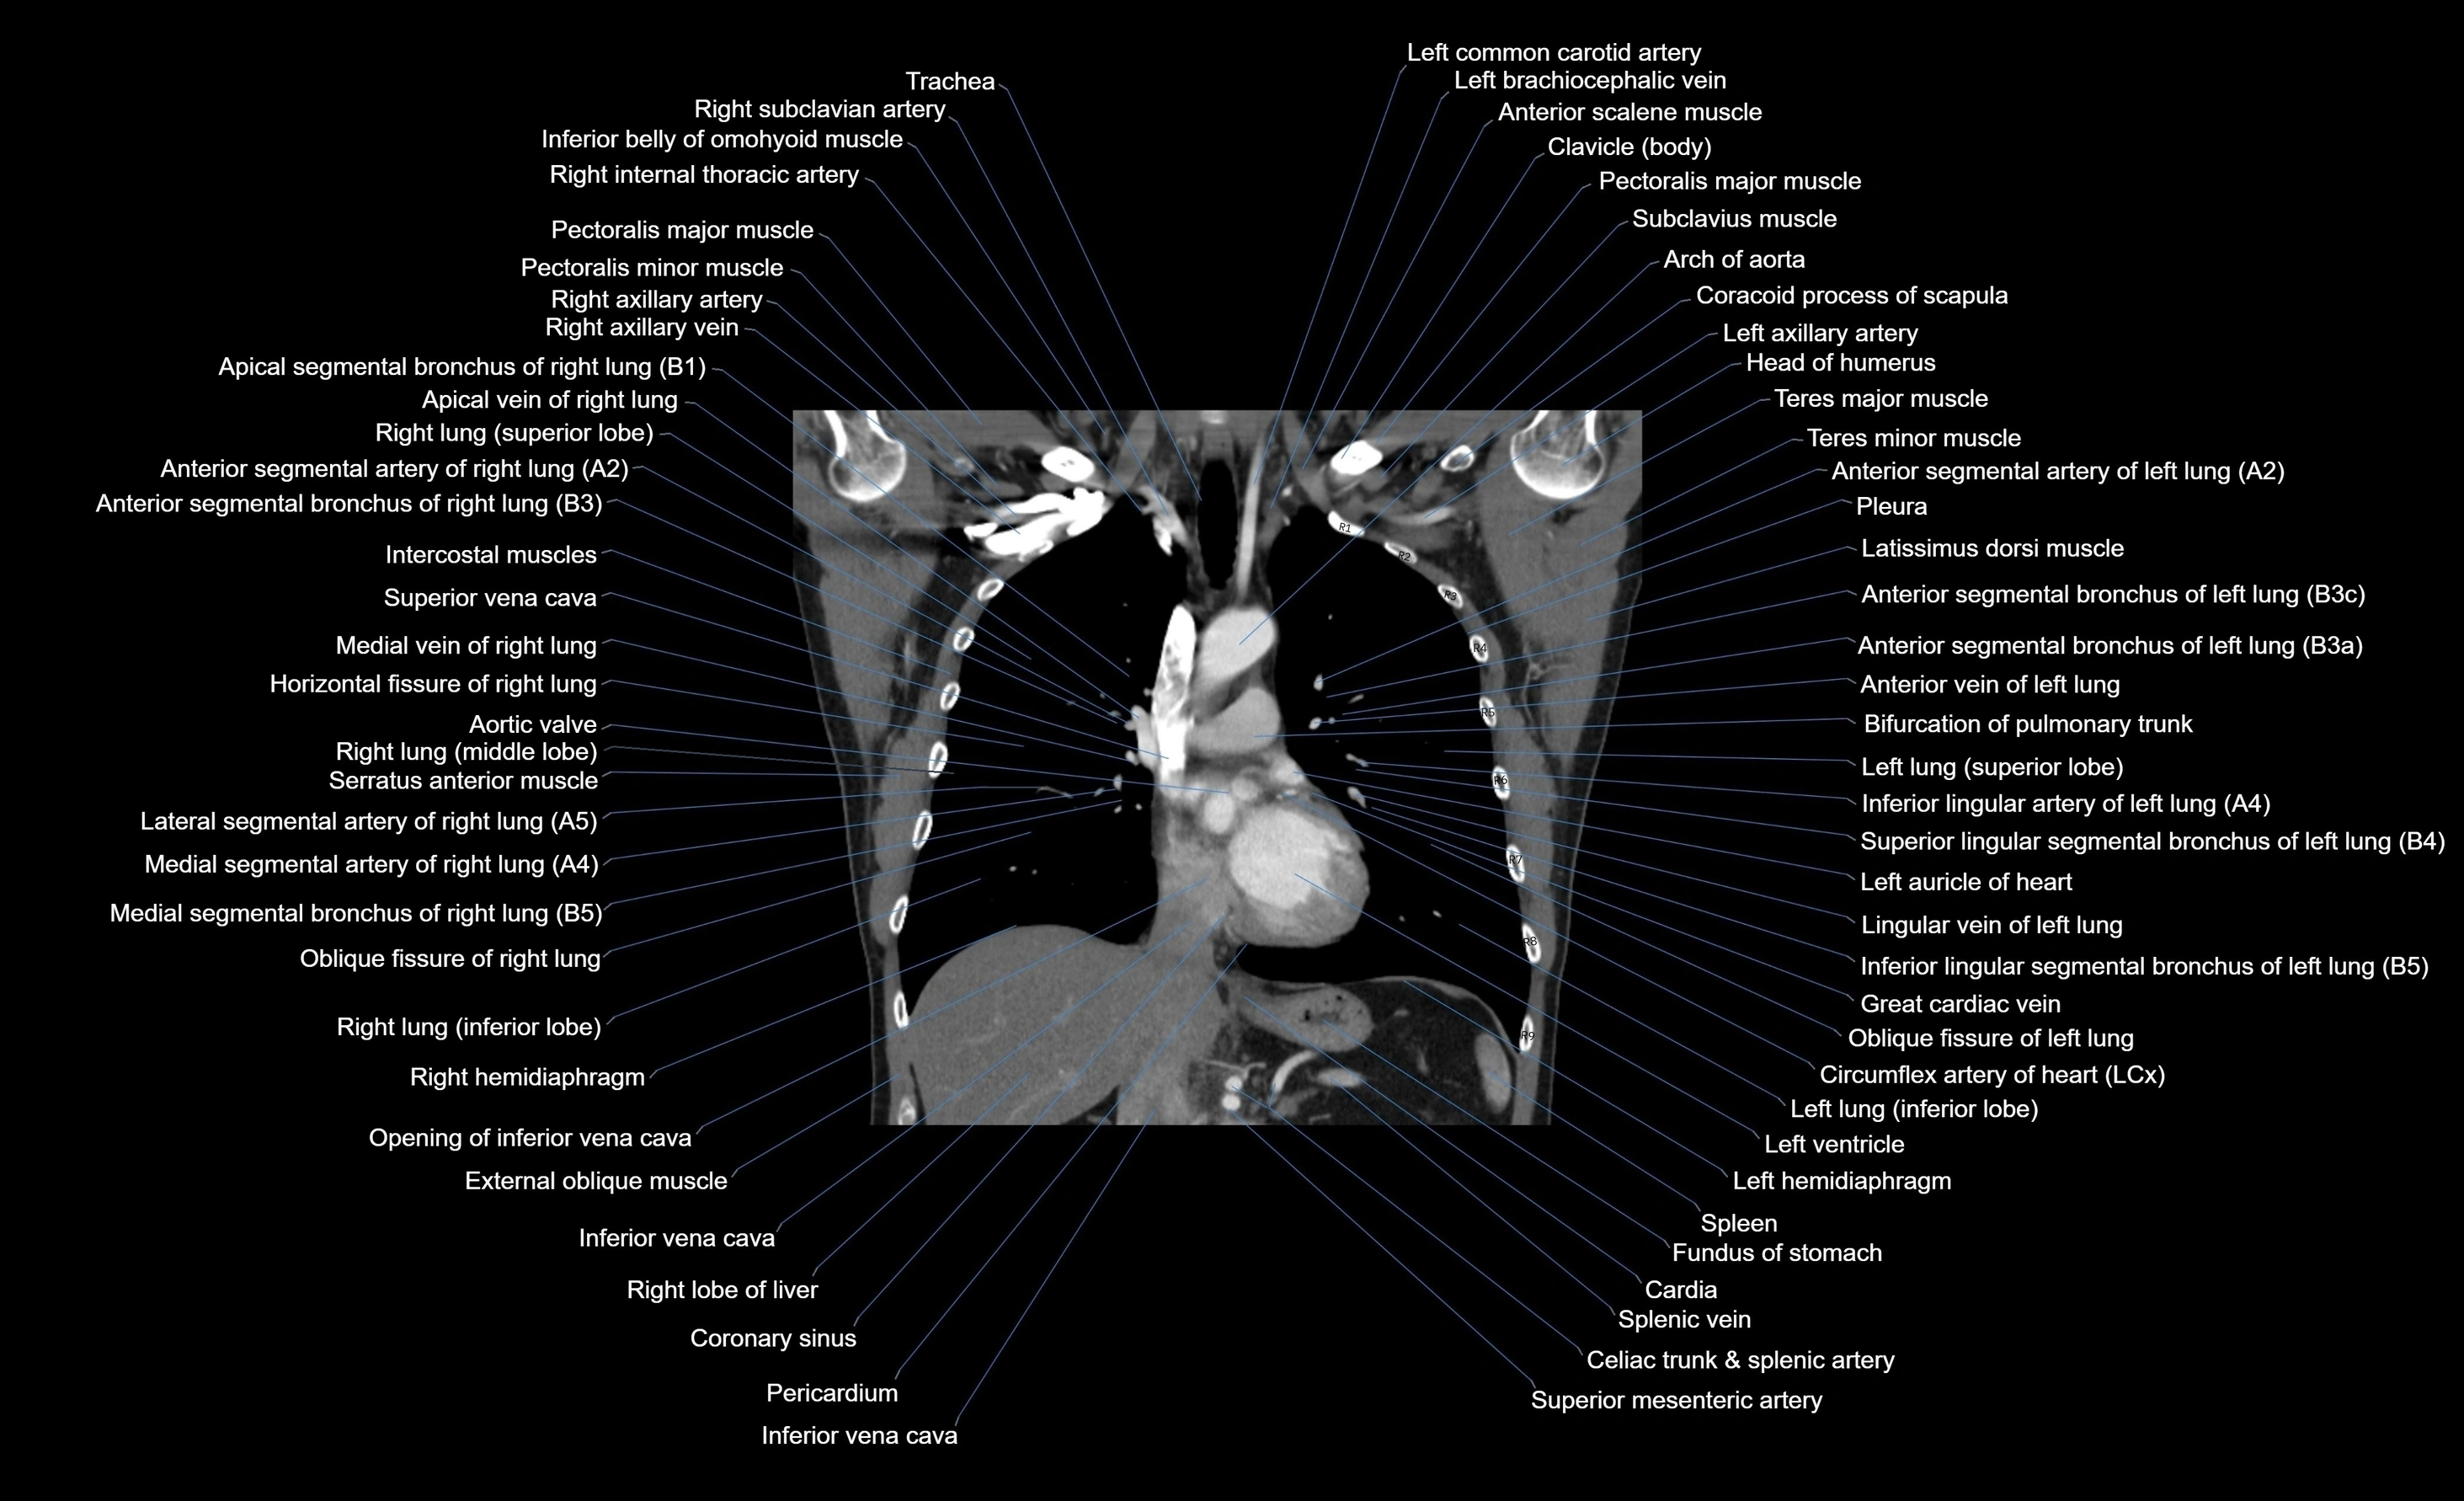

CT images